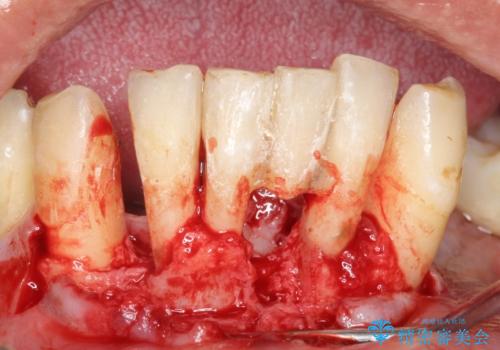

できるだけ自分の歯を残したいという患者様の強いご希望により、禁煙指導後再生療法(骨を増やす手術))を行いました。

再生療法から1年後リエントリー手術により骨の再生を確認し、骨外科処置(骨を平らにして歯周ポケットの根本的な改善を図る処置)を行ったのち、連結補綴を行いました。

骨吸収と動揺が著しい前歯1本(左下1)のみ抜歯しております。